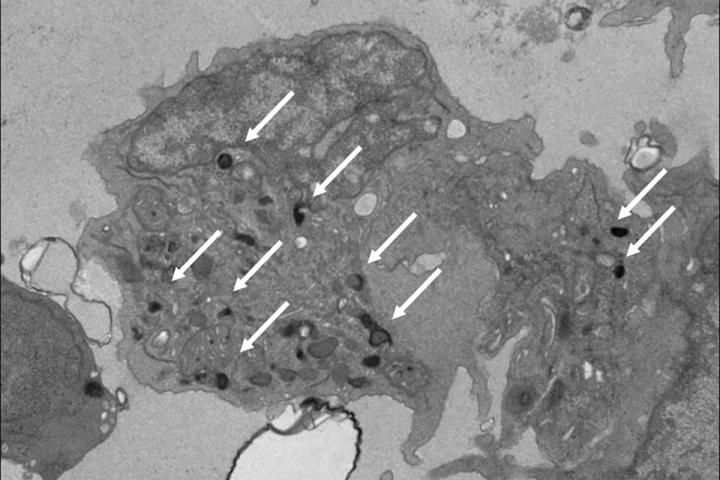

image: Pictured is a natural killer (NK) cell that researchers developed in the lab from human pluripotent stem cells. These NK cells mimic the properties of those found in the yolk sac during the earliest stages of development. Such NK cells may be more effective as immunotherapy for cancer treatment than adult NK cells that come from bone marrow, according to a new study from Washington University School of Medicine in St. Louis. White arrows point out granules that contain potent anti-cancer enzymes. Adult NK cells have very few of these granules.

Studying mouse and human induced pluripotent stem cells that have been coaxed into forming these unique NK cells, the researchers showed that the NK cells are better at releasing specific anti-tumor chemicals -- a process called degranulation -- than their adult counterparts. Even NK cells derived from umbilical cord blood do not respond as robustly. NK cells of adult origin also release different chemicals that trigger harmful inflammation, but this response is not necessarily effective against cancer.